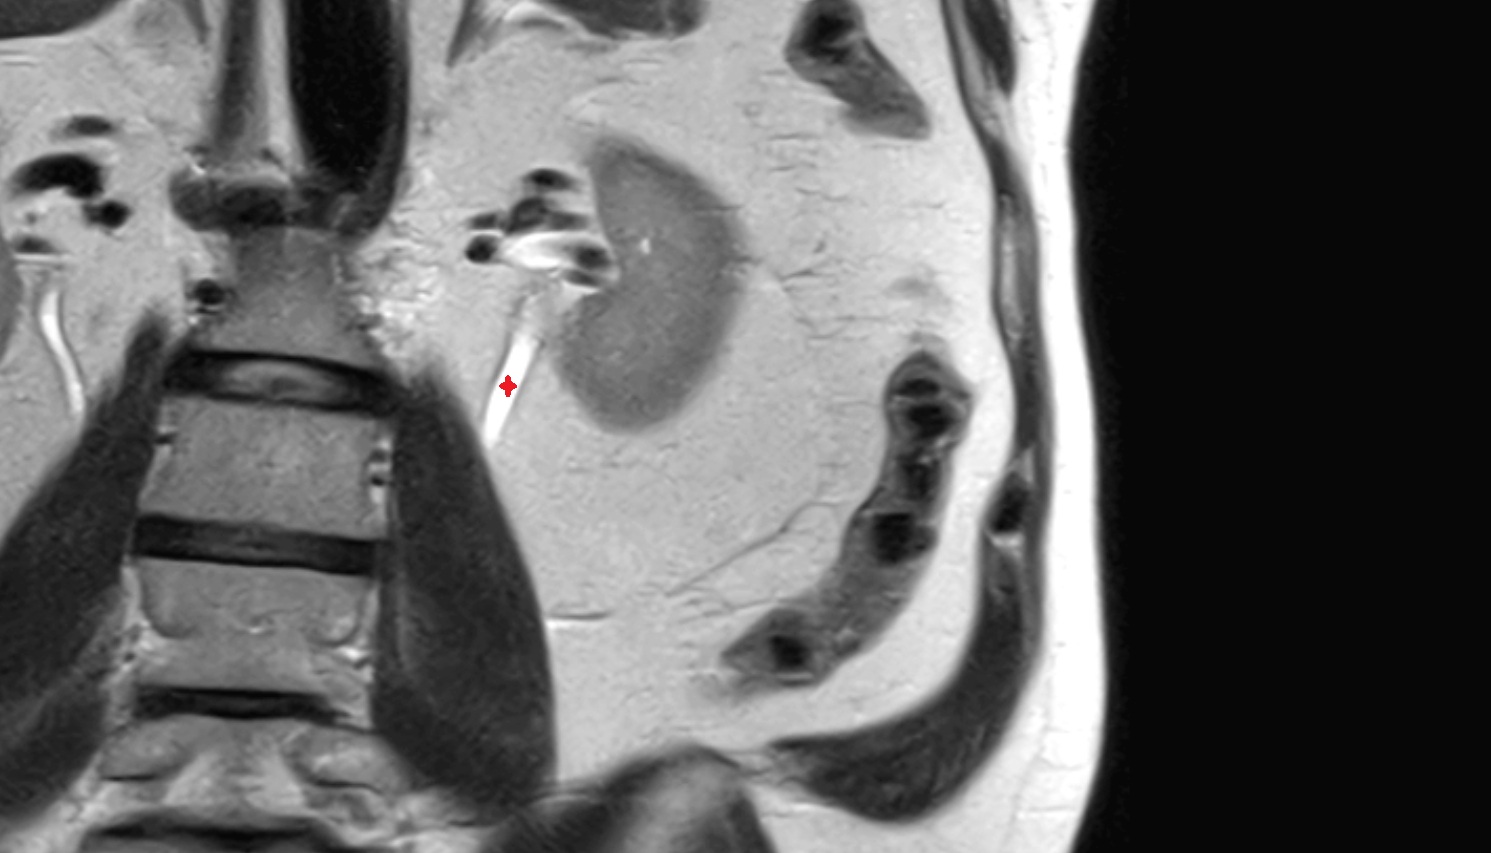

- kidneys

- Right kidney

- Left kidney

- Kidney cortex (Renal cortex)

- Renal medulla

- Renal pyramids

- Renal pelvis

- Renal artery

- Renal vein

- Ureters

- Left ureter

- Right ureter